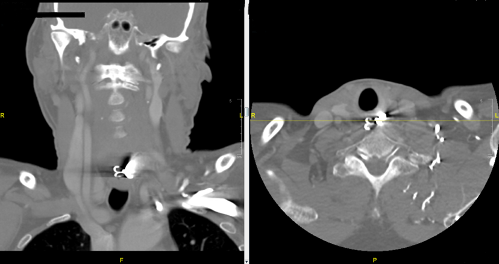

Acting quickly, you assess the patient. He is still not in any acute distress and continues to speak in full, clear sentences without drooling. You do not note any deformities or crepitus on careful palpation of the neck. You do not note any frank blood in his oropharynx, and the rest of his exam is otherwise benign. You decide to call your GI and ENT specialists, who recommend a CT neck and chest. You grab basic labs, including PT/INR, and load the patient up with Zofran and Fentanyl. You do not suspect rupture, and in the absence of fever or leukocytosis you decide to withhold antibiotics. You call the CT scanner to notify them of the patient, and the scan comes back. You take a look:

BOOM! You call both the GI and ENT specialists with the results, who decide to take the patient emergently to the OR for a rigid esophagoscopy with foreign body removal. You continually reassess the patient until they take him back and eventually learn that the operation was successful, and the patient was discharged after several days of monitoring. You sit back down at your desk, sip on your coffee, and prepare to tackle the next case.